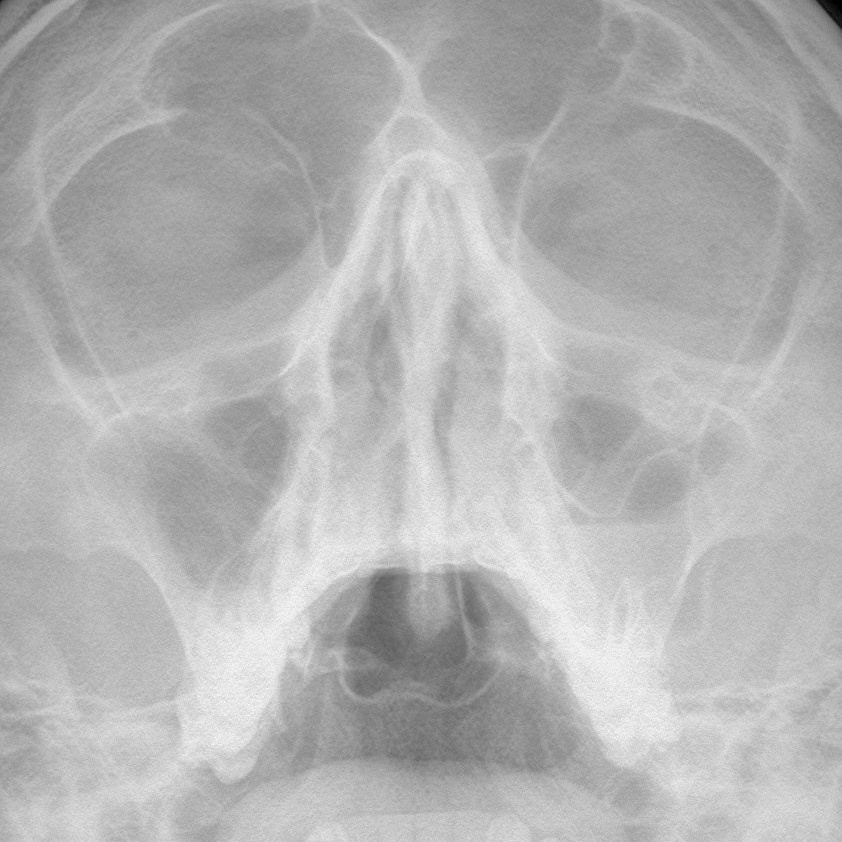

Этот вопрос ставит в тупик не только пациентов, но и бывалых терапевтов, гастроэнтерологов, лор-врачей и многих...